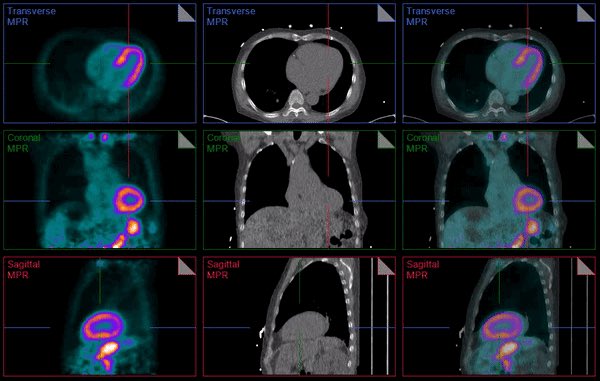

Dr. Edward Miller, MD PhD from Yale Cardiology highlighting🔑 steps in the conduct and interpretation of a Viability study 1/5 Dietary prep (beginning 1-2 days prior to study): goal is to prime the viable myocardium to take up FDG 2/5 Protocol for glucose/insulin injection